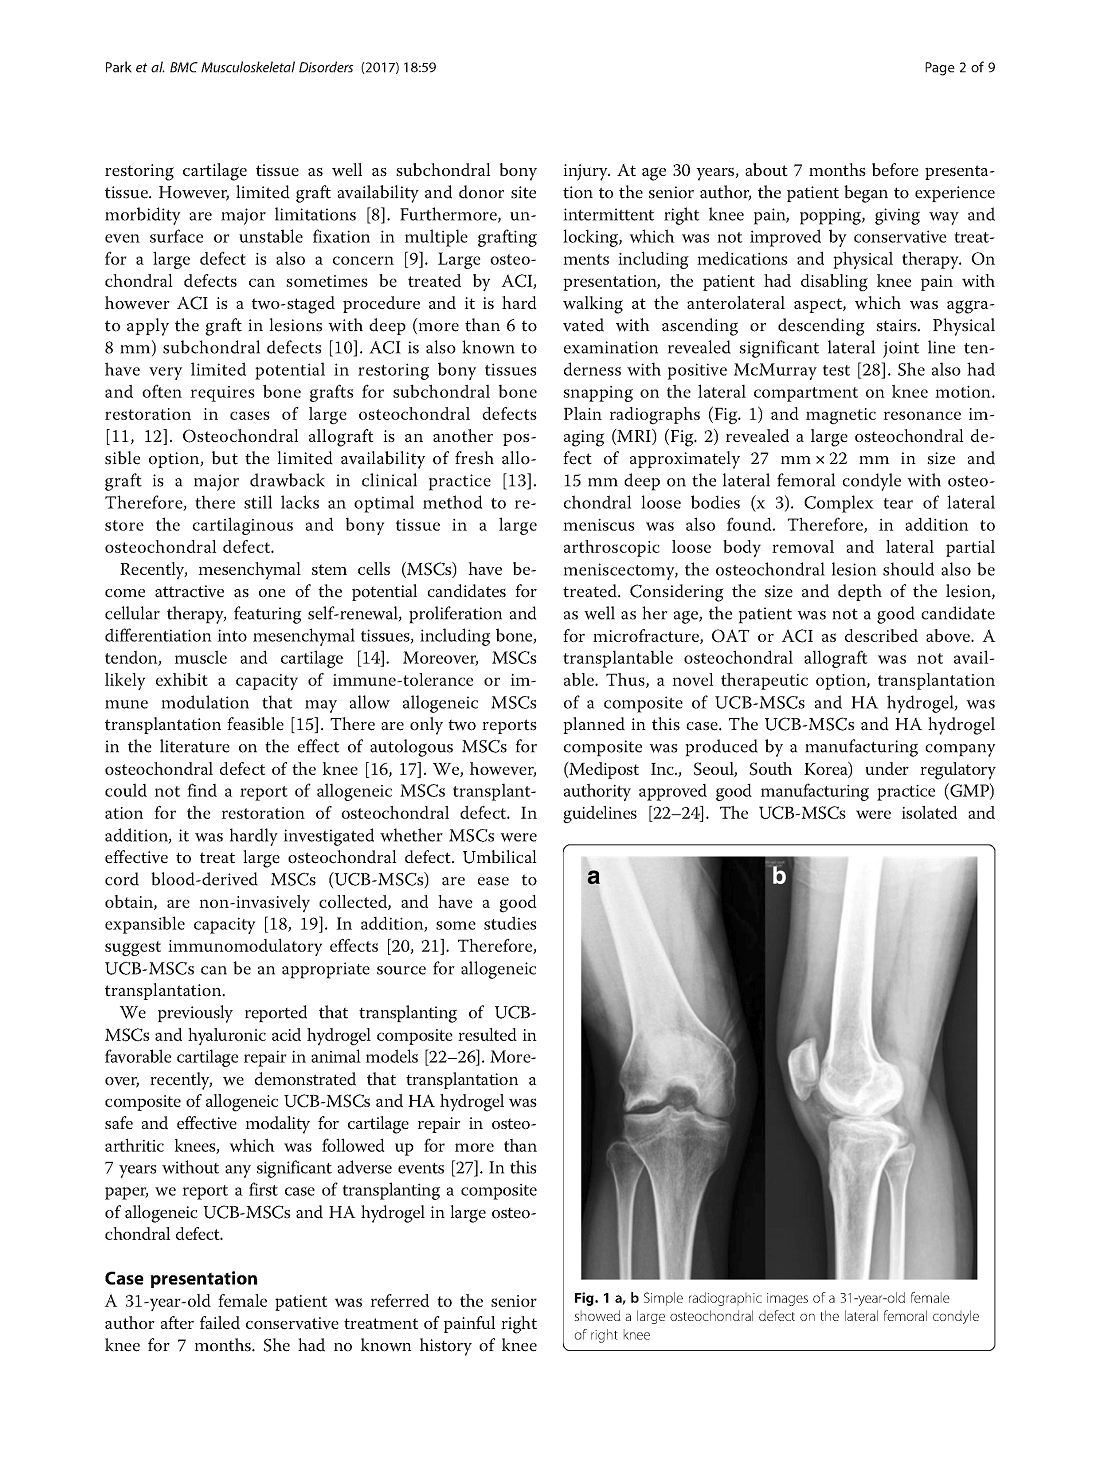

Case presentation: A symptomatic large osteochondral defect in the knee joint was restored using a composite of umbilical cord blood-derived mesenchymal stem cells (UCB-MSCs) 0.5 x 107/ml and 4% hyaluronic acid (HA) hydrogel. Significant improvements in pain and function of the knee joint were identified by the evaluation at 12 months after surgery. A hyaline-like cartilage completely filled the defect and was congruent with the surrounding normal cartilage as revealed by magnetic resonance imaging (MRI), a second-look arthroscopy and histological assessment. The improved clinical outcomes maintained until 5.5 years. MRI also showed the maintenance of the restored bony and cartilaginous tissues.